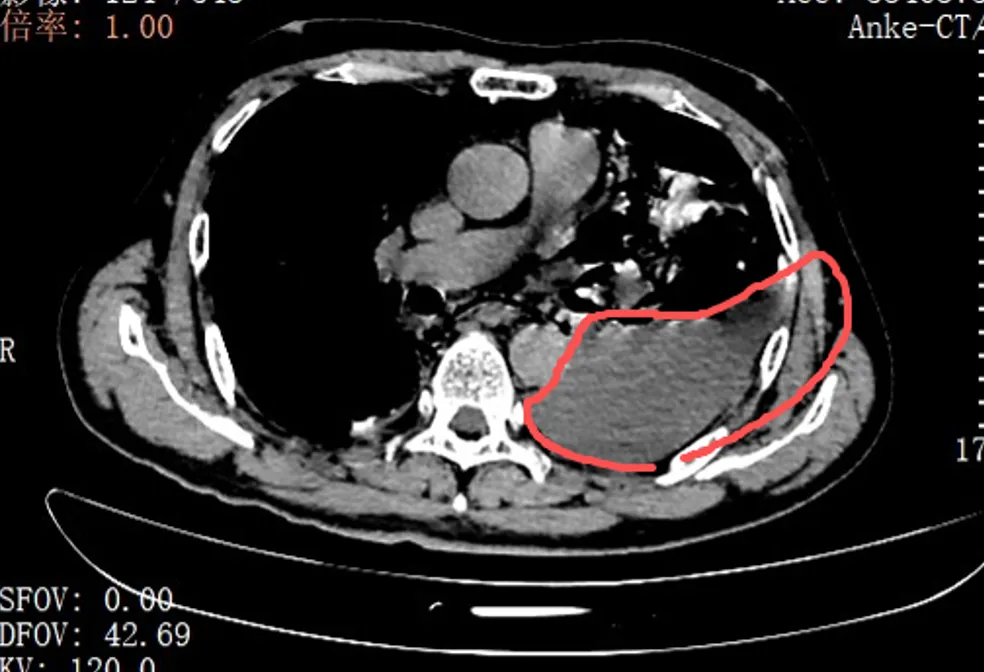

本日,手术团队为张叔实践了胸腔镜下食谈修补微创手术。翻开胸腔的那一刻,在场的医护东谈主员齐呆住了:所有左侧胸腔里,全是叉烧包的菜叶子、食品残渣,混着脓液和消化液,到处齐是。

红圈区域是食品残渣、消化液破入食管

手术团队拿着迷惑器,少许点清算、冲洗,花了很万古期才将胸腔里的每少许食品残渣齐清干净。随后,团队找到了食谈下段那谈长达10公分的裂口,用可招揽线留意翼翼地完成了分层修补。